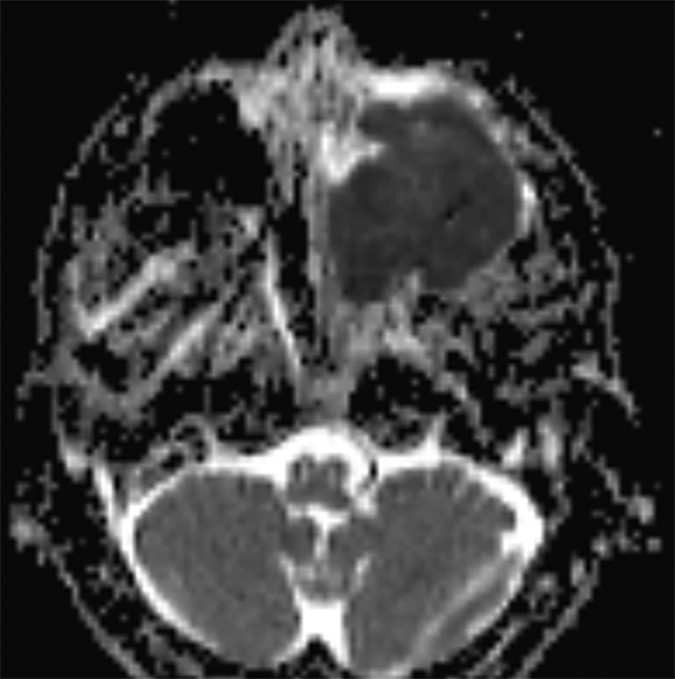

In certain instances, diffusion pulse sequences can offer a complementary adjunct to conventional MR pulse sequences, but neither diffusion-weighted imaging (DWI) or diffusion tensor imaging (DTI) should be utilized as a standalone technique for characterizing the benignity of head and neck lesions. Moreover, since mean apparent diffusion coefficients (ADC) values derived from DTI parameters are characteristically lower than ADC values developed from DWI parameters—frequently lower than reported malignant threshold values—the two should not be used interchangeably (Fig. 3).